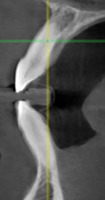

При анализе и описании компьютерной конусно-лучевой томографии (рис. 2а-г) была выявлена генерализованная первичная дегисценция вестибулярной пластинки кости от 1/2 до 3/4 длины корней зубов, зубной ряд целостный, все зубы витальны, кариозных поражений нет. Тип кости 1-2 (Lechkolm и Zarb, 1983), первичная дегисценция вестибулярной костной пластинки превышает пределы возрастной атрофии.

10. Анализ компьютерного томографического обследования

Через 12 месяцев (рис. 7а-г) на срезах компьютерной томограммы 11-ый и 13-ый зубы находятся в костной ткани, при этом костные пики и перегородки укрепились, объем их увеличился; вестибулярно заметен объем костной массы, предположительно компактной формации, исходя из электронной плотности участка. Этим объясняется отсутствие рецидива при лечении рецессии десны как в случае применения аутотрансплантата, также и ТМО (dura mater).